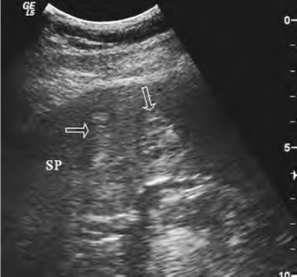

①脾血管瘤:脾实质内单个或多个,边界清晰,多呈不均匀的强回声区,亦可呈网格状(图24-3)。

图24-3 脾血管瘤声像图

箭头示血管瘤,内回声呈网格状。SP:脾脏